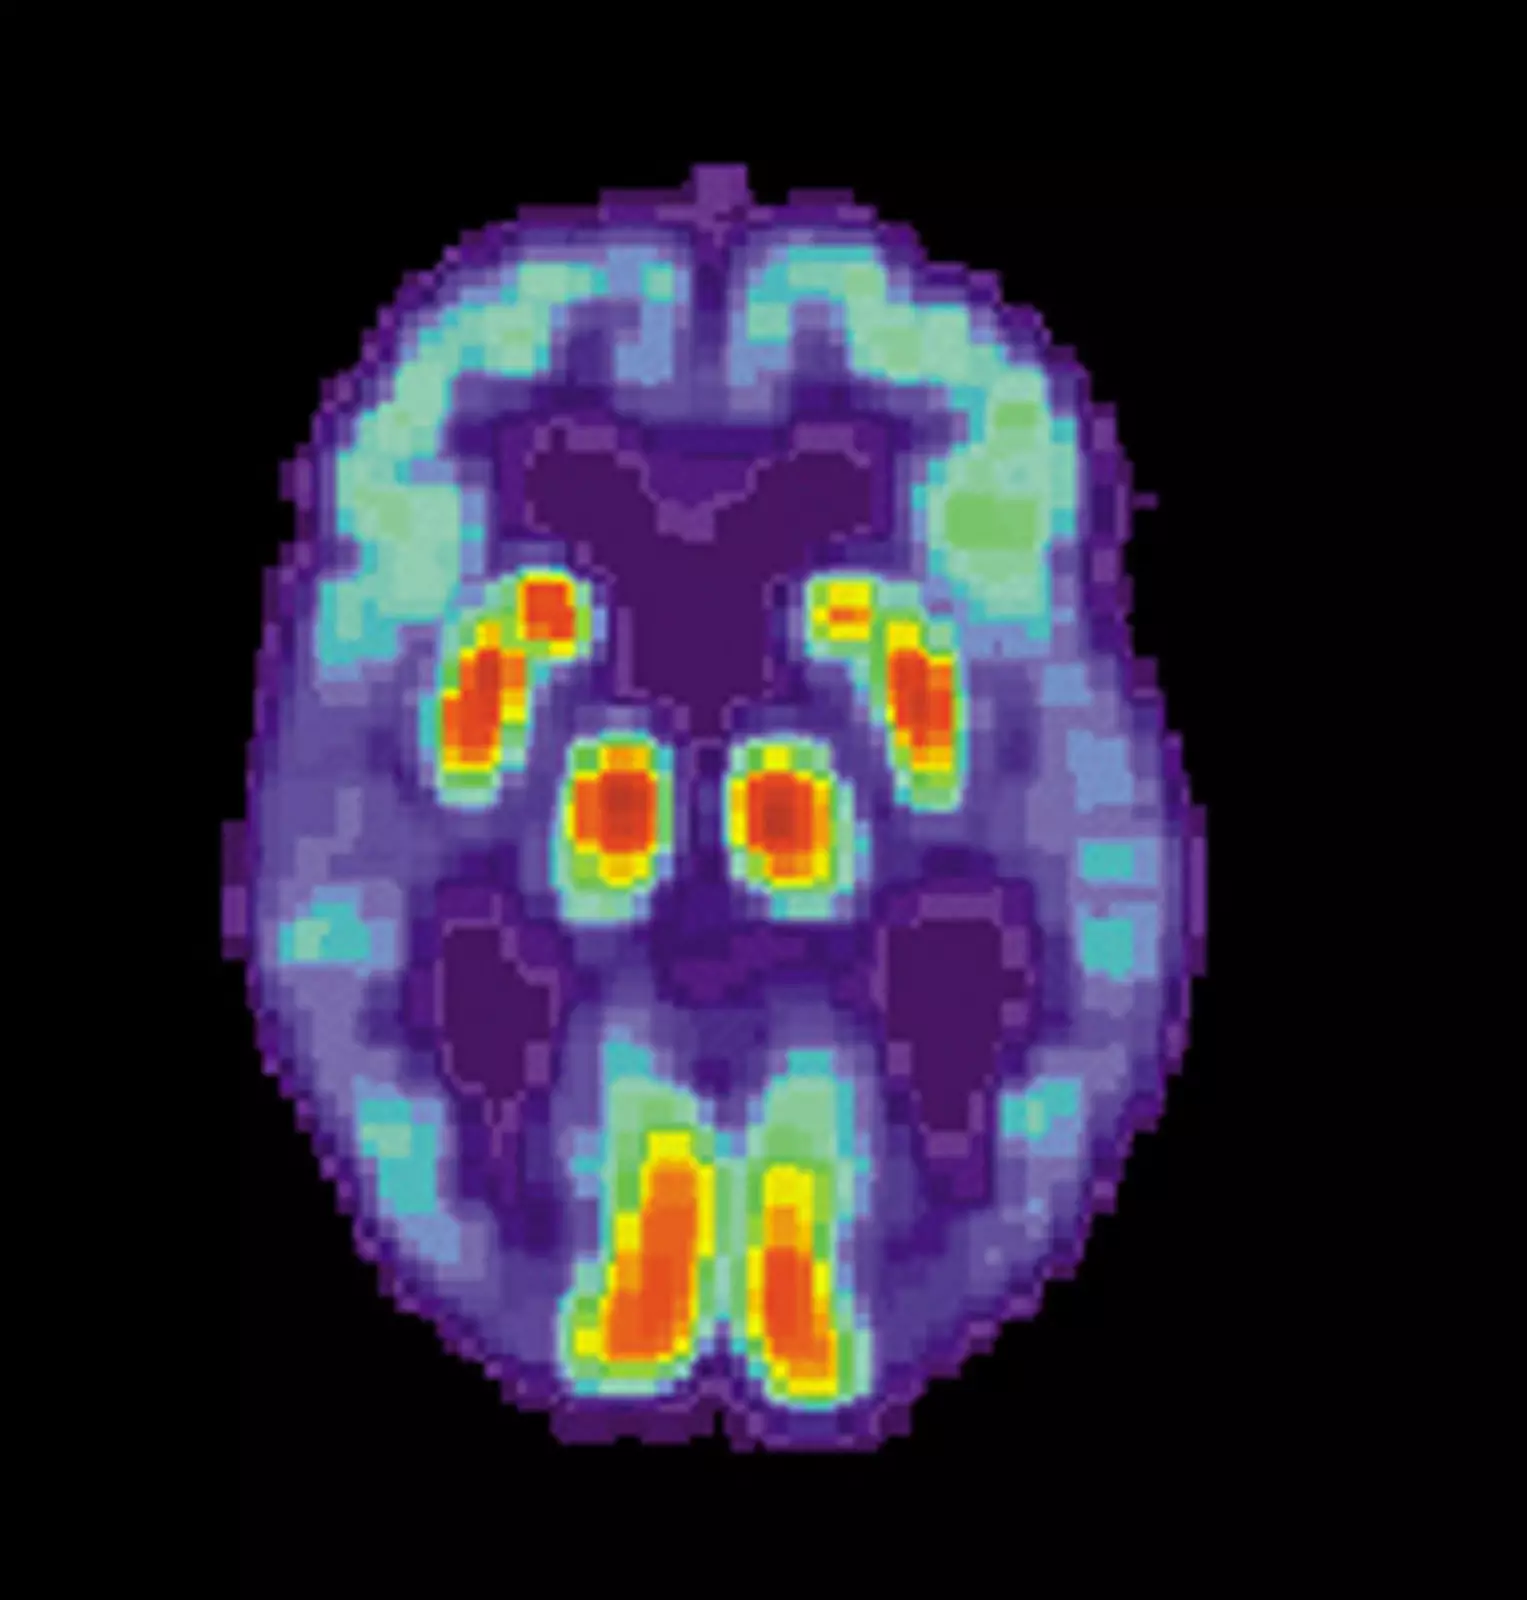

Появление позитронно-эмиссионной томографии (ПЭТ) позволило ученым воочию понаблюдать за потерей синапсов у живых пациентов даже с легкими симптомами болезни Альцгеймера.

Новый ПЭТ-визуализатор с использованием гликопротеина 2A (SV2A) помог измерить метаболическую активность в синапсах головного мозга у 45 человек с болезнью Альцгеймера легкой и средней степени тяжести.

ПЭТ-снимок головного мозга.